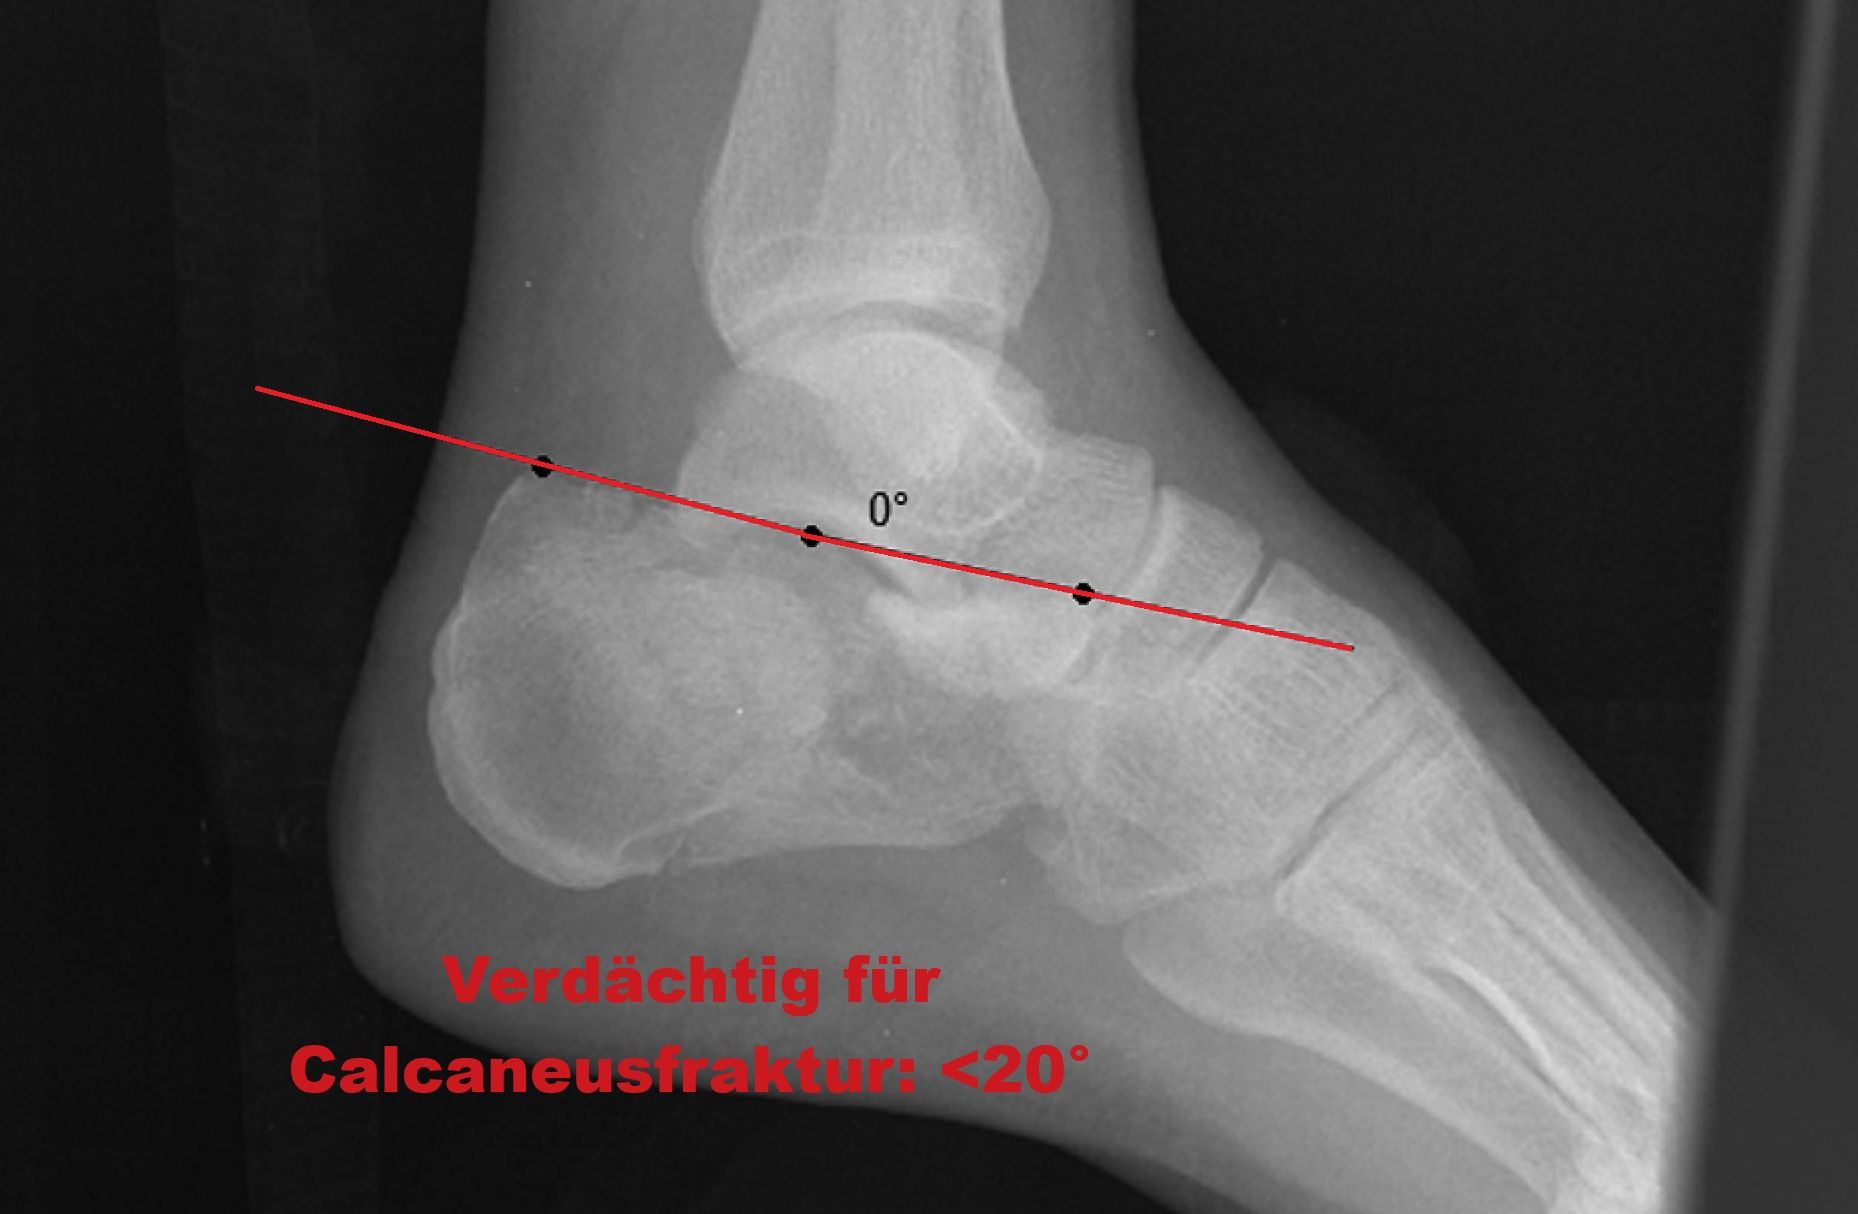

Böhler Winkel

boehler-winkel-pathologisch